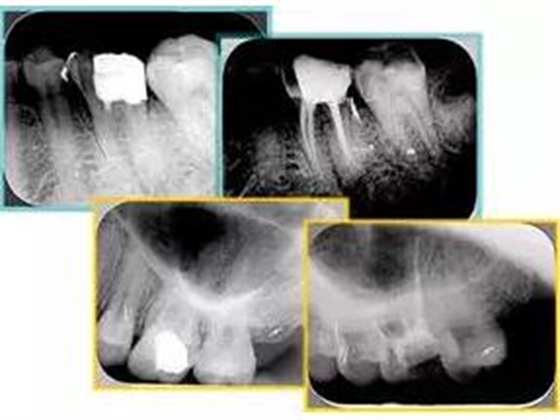

6. 術(shù)后 X 線(xiàn)片

術(shù)后 X 線(xiàn)片用來(lái)評(píng)定根管充填 長(zhǎng)度、致密度(管壁清晰、側(cè)枝)等指標(biāo)。

左圖為根管充填術(shù)后 X 線(xiàn)片。圖中可見(jiàn),根管充填較好。右下圖有白色小點(diǎn),為側(cè)方加壓導(dǎo)致糊劑擠出所致,表明根管充填比較致密。

致密、恰到好處的充填可去除干凈根管里感染灶,機(jī)體逐漸恢復(fù)。

多根牙時(shí)候需進(jìn)行偏移投照,正位投照無(wú)法說(shuō)明具體哪根牙根管充填效果。